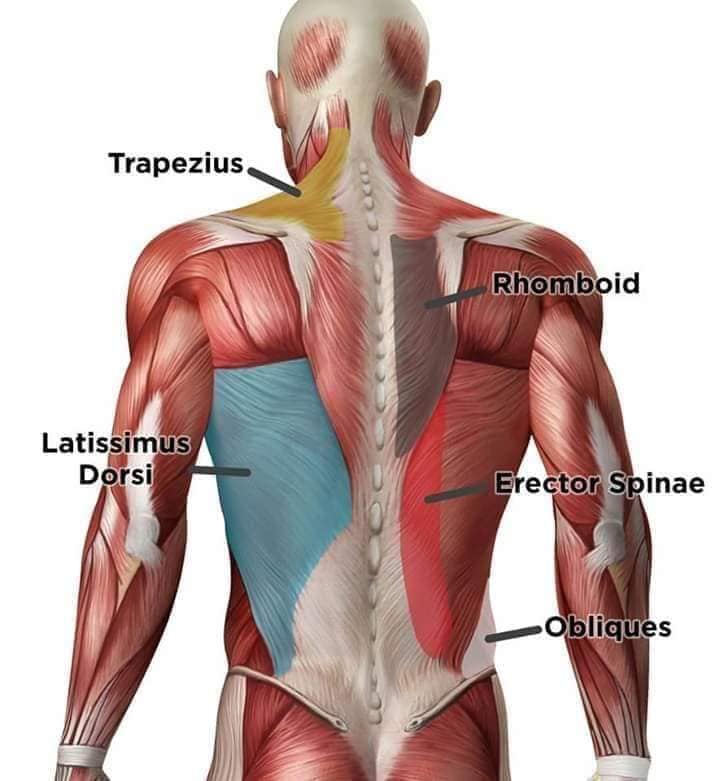

М'язи, що розширюють шию: М'язи, що розширюють шию: включають трапецієподібний м'яз, який бере участь у піднятті плечей і розширенні шиї.

Спинні м'язи виконують функції підтримки хребта, а також дозволяють здійснювати рухи тулуба.

Поверхневі спинні м'язи

М'язи, що піднімають лопатку: Трапецієподібний м'яз: великий м'яз, що покриває верхню частину спини. Його функція - підтримка і рух лопаток, а також забезпечення стабільності хребта.

М'язи, що ведуть лопатку до хребта: Широкий м'яз спини: великий м'яз, що розташований в нижній частині спини. Він відповідає за рухи плечей і лопаток, а також за розширення верхньої частини тулуба.

Глибинні спинні м'язи

М'язи, що забезпечують стабільність хребта: М'язи, що розташовані між хребцями: включають мускулатуру, яка забезпечує стабільність і підтримку хребта, а також дозволяє здійснювати рухи хребта.

М'язи, що здійснюють ротацію та нахили

М'язи, що забезпечують ротацію хребта: Ротаційні м'язи: допомагають у здійсненні обертальних рухів тулуба, а також у підтримці рівноваги і стабільності хребта.